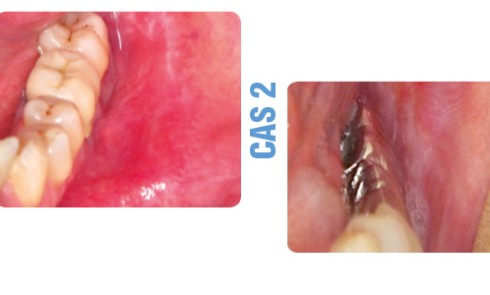

Article réservé à nos abonnés Ulcérations palatines postérieures trompeuses !

CAS 1 Motif de la consultation.Patient de 25 ans, venu consulter pour l’apparition d’une lésion douloureuse sur le palais. Histoire...